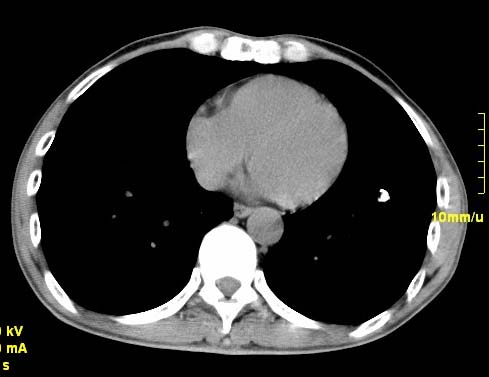

以下是引用wangzhengyuan在2007-11-11 23:31:00的发言:[br]钙化灶,看上去不像转移。

以下是引用zjzjr在2007-11-12 8:35:00的发言:[br]考虑错构瘤,建议定期复查.

以下是引用卜一在2007-11-12 5:59:00的发言:[br]病灶本身不像转移,不知有没有以前的胸部ct片,若有,则可以对比以下,若是新出现病灶,应高度警惕“转移”的可能![br]